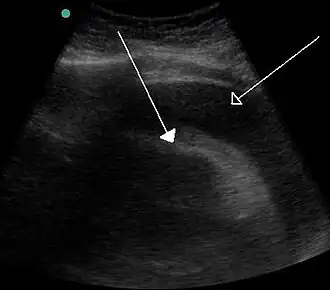

![]() Un derrame pericárdico muy grande que resulta en un taponamiento como resultado del sangrado por cáncer, como se ve en la ecografía. Flecha cerrada - el corazón; flecha abierta - el derrame | ||